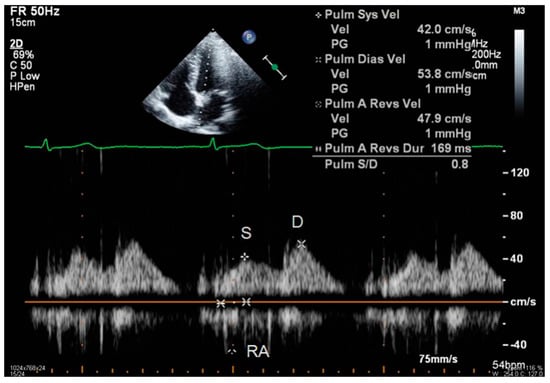

- S and D wave peak velocity on right superior pulmonary vein flow in pulsed Doppler (Figure 6);